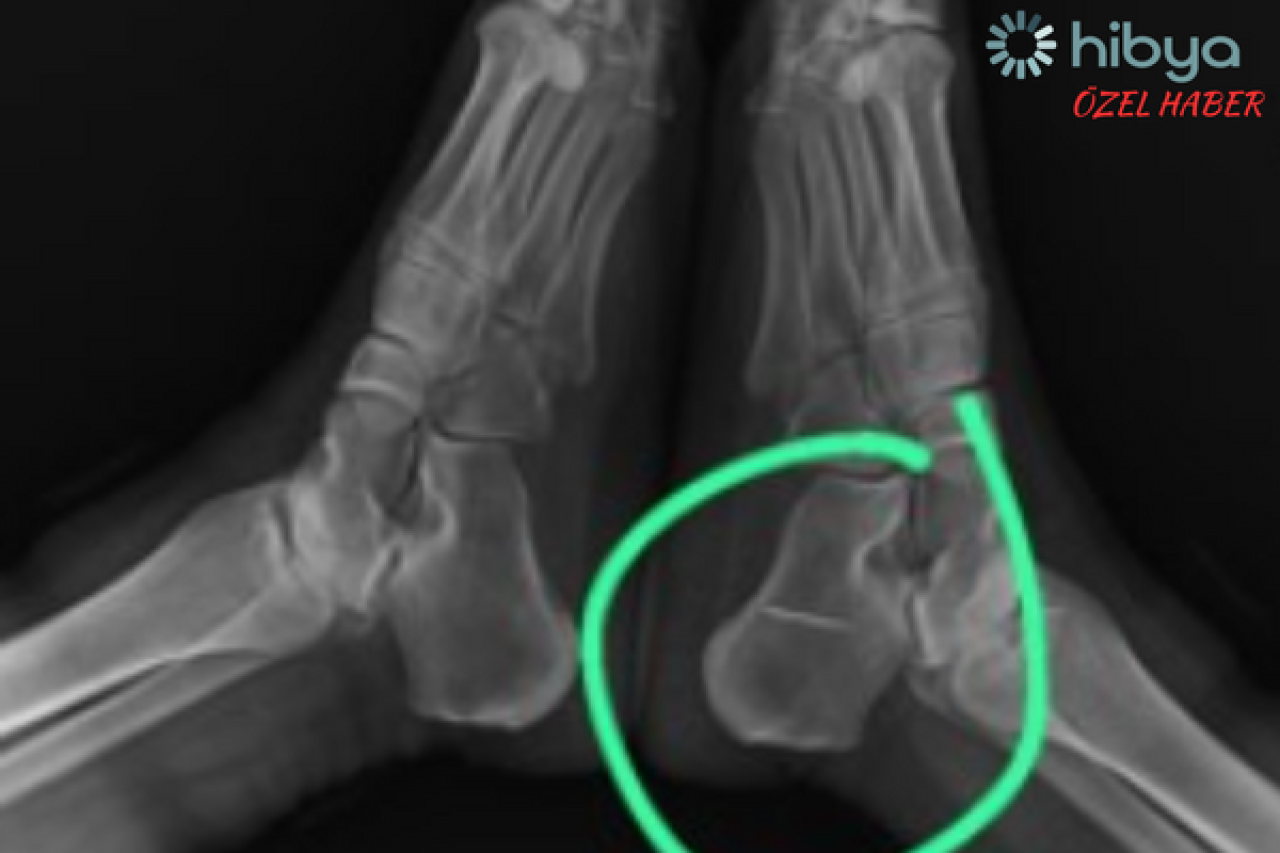

Röntgen sonucunu inceleyen doktor, Semra S'nin ayağının topuk kemiğindeki dikiş iğnesini görünce gözlerine inanamadı.

Hastasına bilgi vermesinin ardından, iğnenin kemiğe saplandığını ve hareket etmediği belirleyen acil servis hekimi, herhangi bir işlem yapılmasa da söz konusu iğnenin sorun yaratmayacağını iletti.